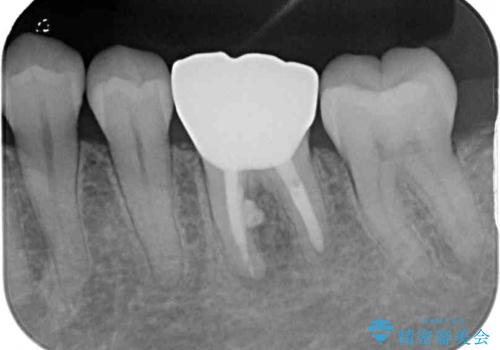

処置後、下顎の膿の出口はすぐに消えましたが、レントゲン写真からも分かるとおり、歯根途中に穴が開いており、充填材が歯根外にはみ出していました。数ヶ月経過を見たところ、特に異常は認められなかったため、補綴治療を行いました。